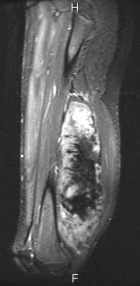

J.G. - 14 year old male c/o left posterior thigh mass for eight months. His mother noticed the mass, but no ecchymosis, after he fell while running hurdles. He complains of pain only when running long distances, and with prolonged pressure. It has decreased in size only minimally. No F/C.